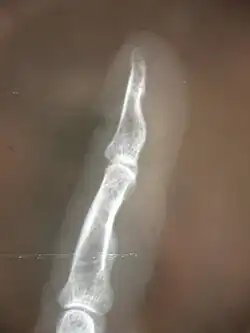

La luxation articulaire est définie comme un déplacement évident entre deux os. La subluxation est un processus plus discret de déplacement entre deux articulations, pas nécessairement décelé sur une radiographie ou une imagerie à résonance magnétique.

Subluxations des membres périphériques

Celles-ci suivent également la règle précitée de subluxation articulaire avec des conséquences neurologiques dans certains cas. Néanmoins, les conséquences de déplacements osseux sur les parties périphériques du corps sont souvent beaucoup plus prévisibles en termes de conséquences sur les fonctions nerveuses, tant au niveau moteur qu'au niveau sensoriel, ou encore pour ce qui est des fonctions végétatives (épidermiques et circulatoires notamment)

De même, lorsqu'une structure comme l'articulation ulno-radial (coude) se retrouve partiellement déplacée ou réduite en mobilité, le nerf radial peut subir une compression induite par le radius lui-même ou induite par l'hypertonicité des muscles environnants, réduisant ainsi ses fonctions sensorielles ou motrices. Une manipulation spécifique sur le radius aura l'effet de décomprimer le nerf incriminé, les effets sensoriels ou moteurs seront alors modifiés, soit instantanément soit sur une période allant jusqu'à 76 heures.